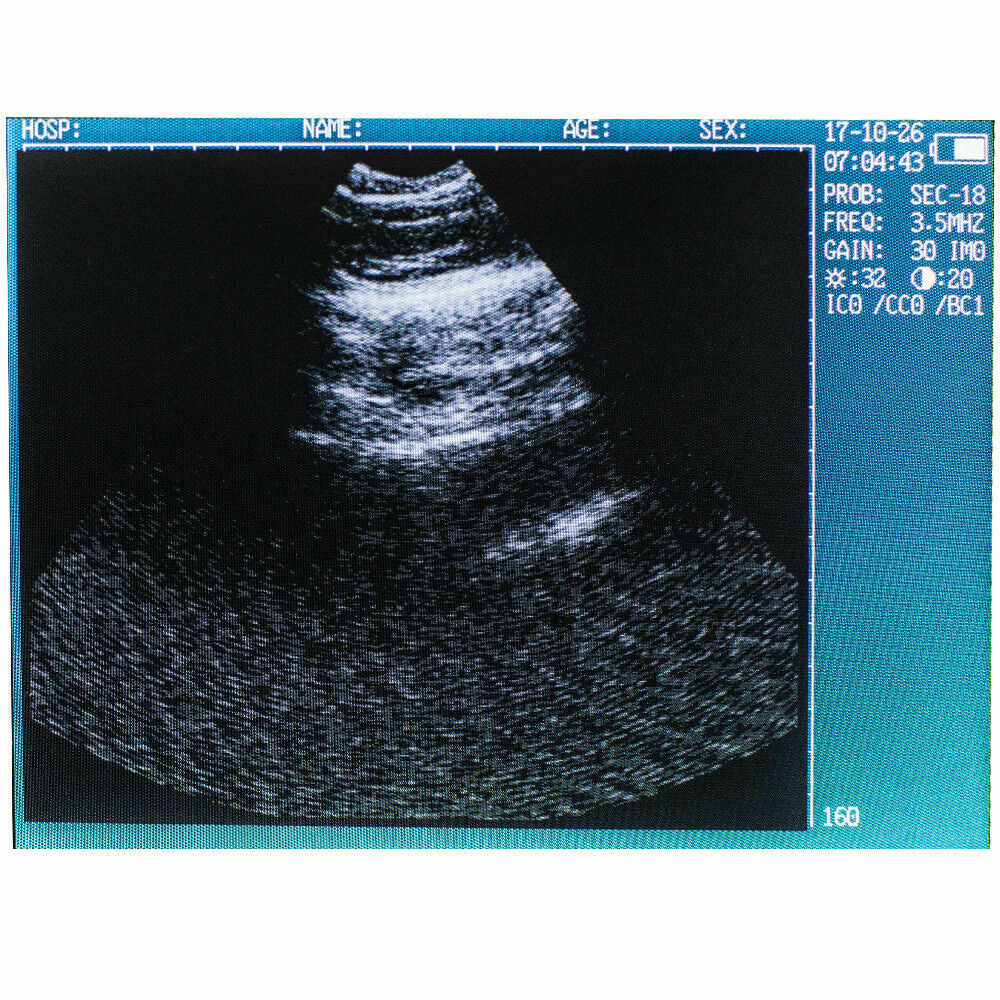

The Veterinary Vet Ultrasound Scanner Machine System Kit for Pregnancy Animal Use is a specialized diagnostic tool designed to monitor the health and development of animals during pregnancy. This portable and user-friendly ultrasound system is ideal for veterinarians, farmers, and animal clinics, enabling quick and accurate pregnancy detection and monitoring in a variety of animal species, including cattle, sheep, pigs, dogs, and horses.

The system typically comes with a probe that is specifically designed to provide clear imaging of the animal’s reproductive organs, allowing the veterinarian to determine the pregnancy status, number of fetuses, and their development stages. With real-time imaging and high-resolution capabilities, it helps in assessing the health of the fetus and identifying potential complications. The machine is lightweight and portable, making it easy to use on farms or in field environments. This ultrasound system is a valuable tool for ensuring the health and wellbeing of pregnant animals and managing breeding programs efficiently.